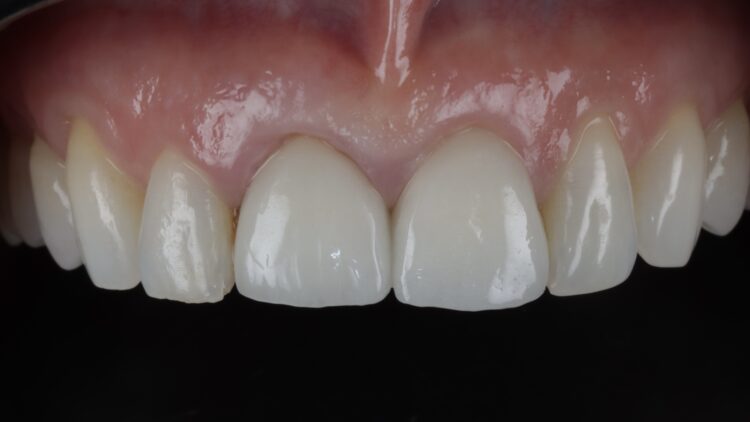

Upon review eight weeks later, healing had been uneventful. The temporary restoration will be left in place for six months to allow the tissues to mature prior to final restoration.

A key factor in this case was the patient’s occlusion. The deep overbite made immediate loading a higher risk, so a guided workflow was crucial to ensure primary stability was not lost. Occlusion, parafunction and bruxism are all critical factors when assessing for implant placement, especially alongside immediate loading.

The CONELOG® implant system is my go-to for immediate cases, particularly where strength and function must be balanced with aesthetics. Its long conus reduces micromovements and it affords greater positional stability than other conical systems I have used. The 3.8mm diameter is the ideal combination of surgical strength and aesthetic considerations. The Guided Surgical Kit is simple to use and has a streamlined workflow for increased efficiency.